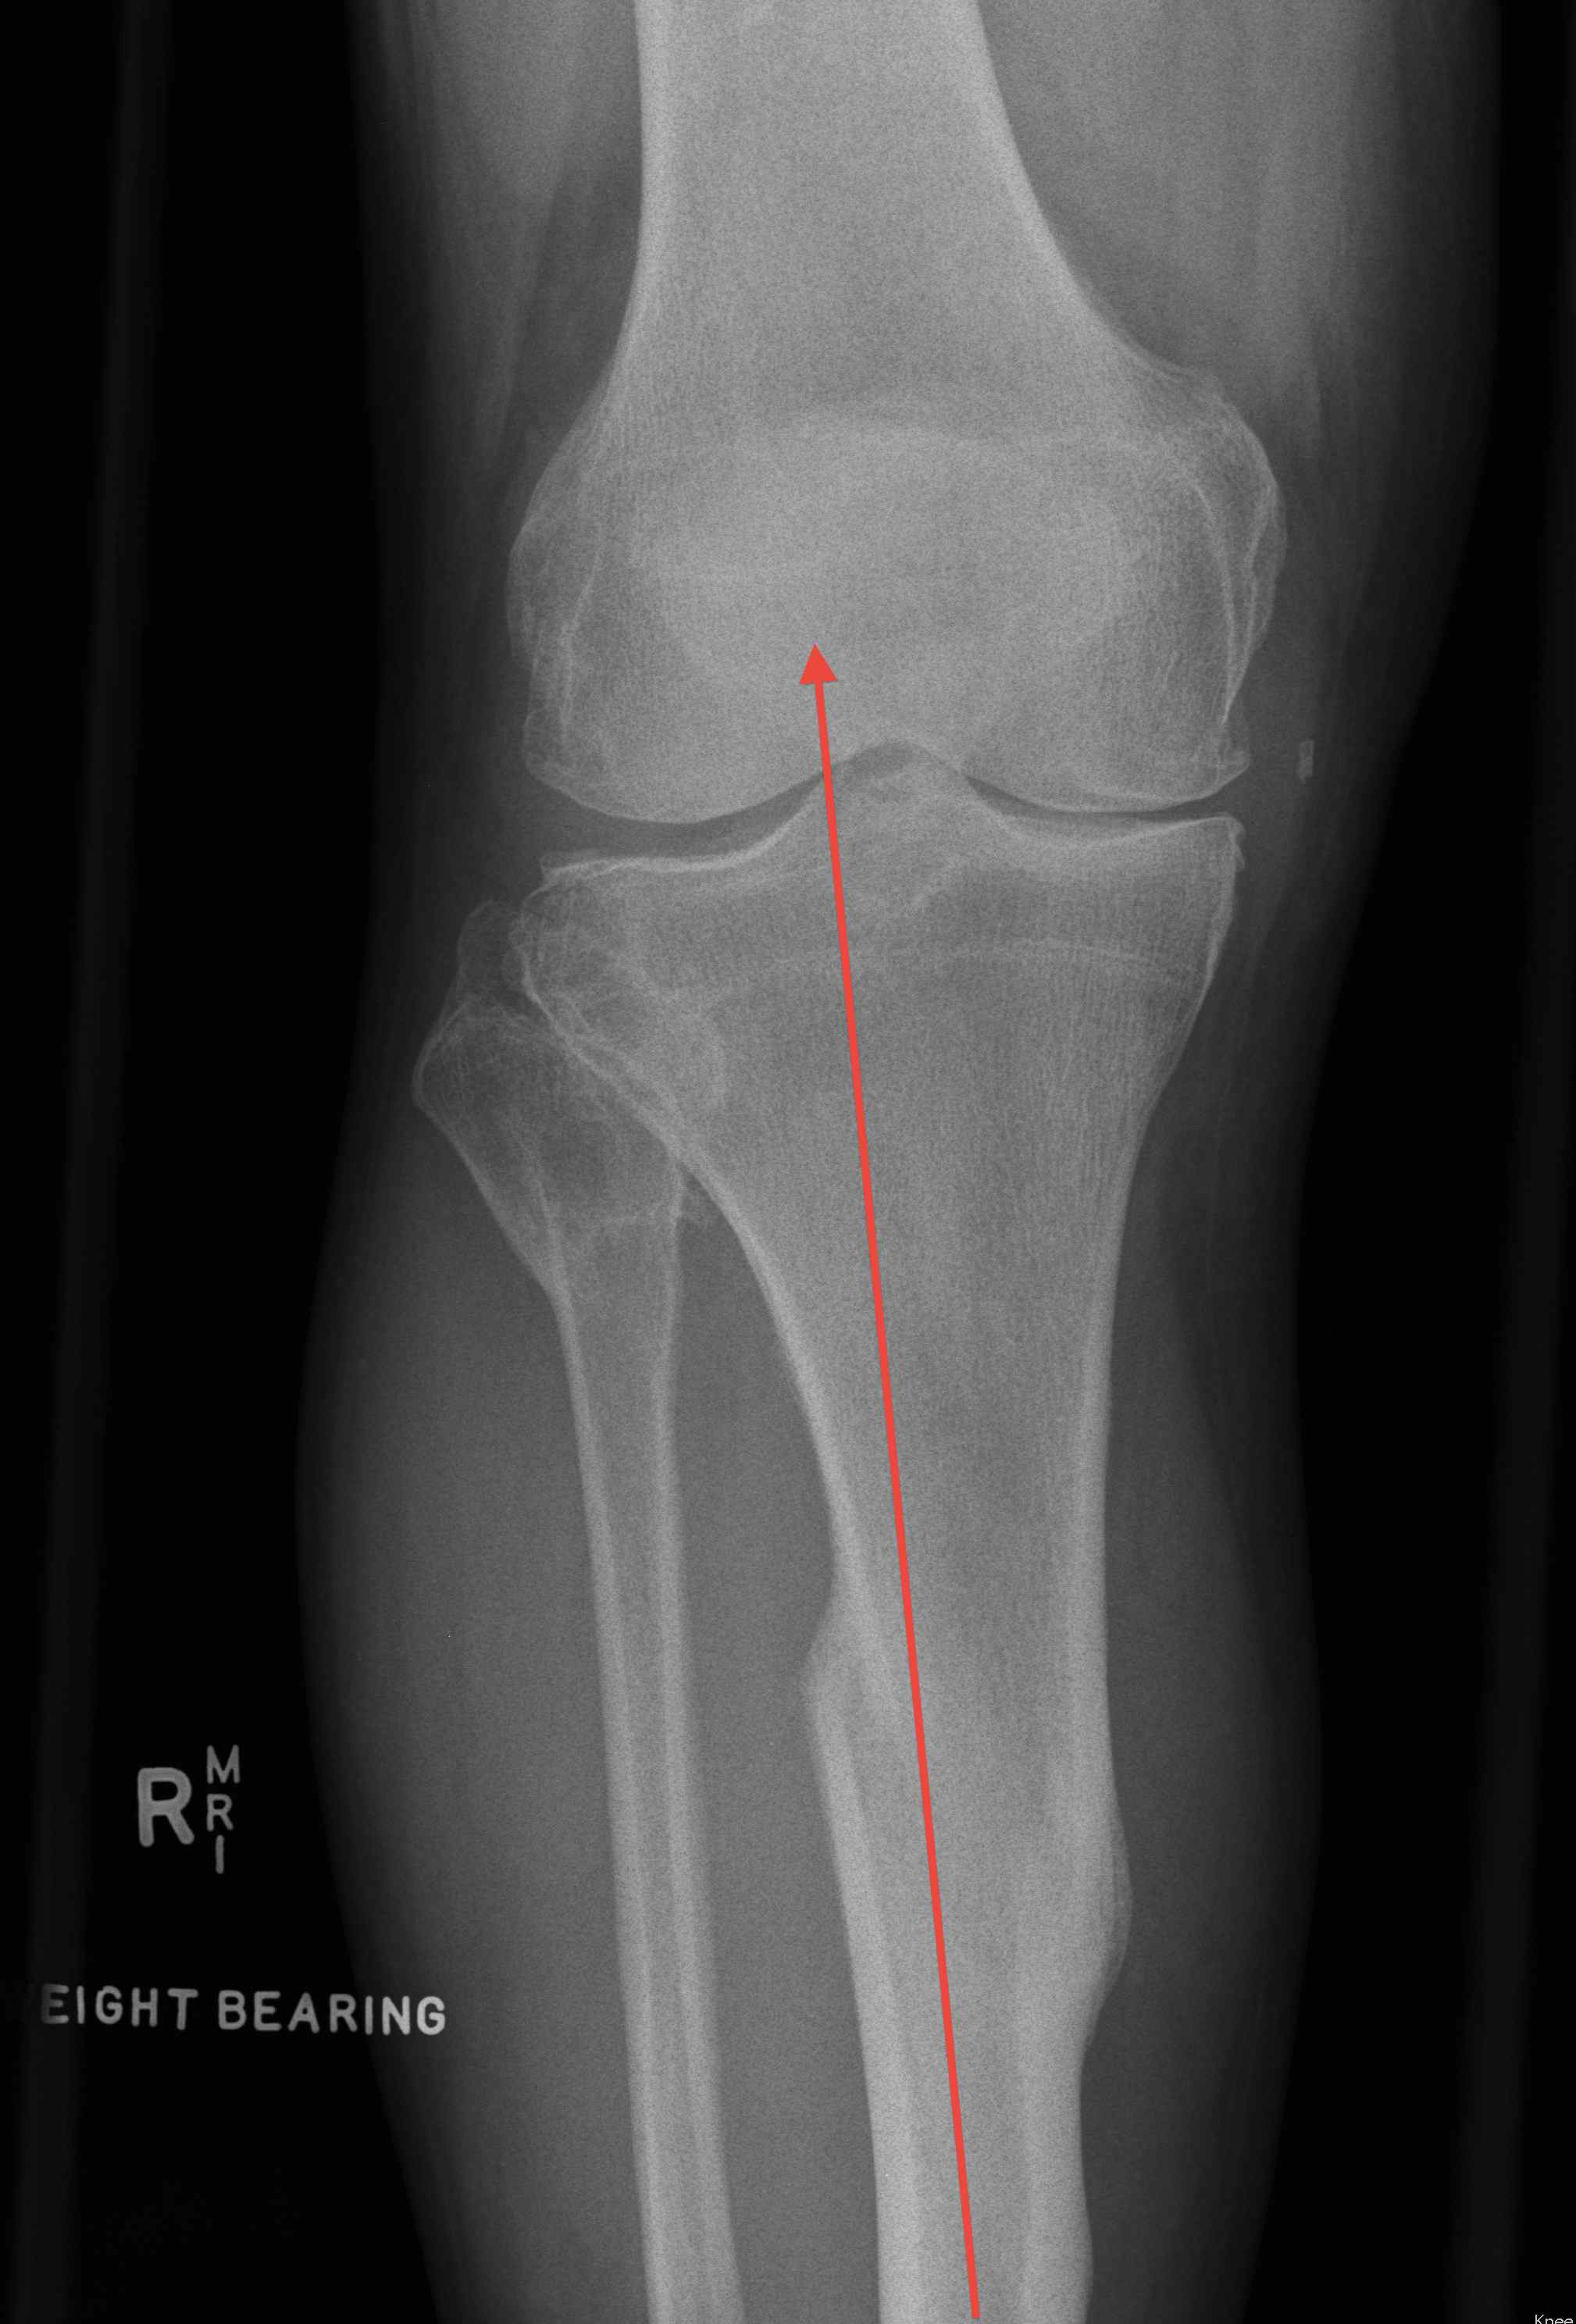

Femur

- draw line of mechanical axis of femur

- line perpendicular to this / proposed distal cut

- this line must pass below insertion of collaterals

- sagittal and coronal planes

Max 20˚ coronal plane

Tibia

- line drawn medullary canal of distal segment

- must pass between condyles

- maximum 30˚ varus